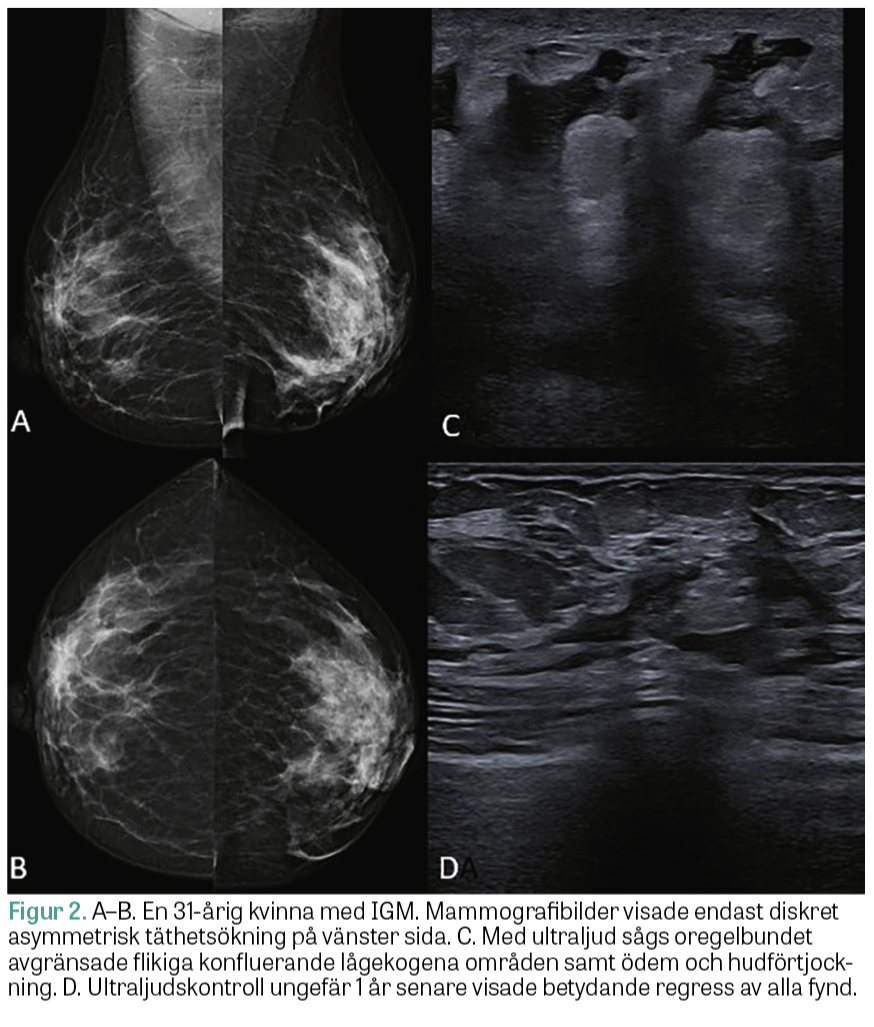

De vanligaste mammografiska fynden är fokal asymmetrisk täthet eller oregelbundet avgränsade förtätningar (Figur 2 A–B). Ytterligare fynd är axillär lymfadenopati, fokal hudförtjockning, ödem samt indragen mamill, vilket även kan observeras vid bröstcancer [2, 3, 10, 11].

Ultraljud är den primära bilddiagnostiska modaliteten för patienter med mastitsymtom, oavsett ålder. Ultraljud används för att utföra biopsier och vägleda terapeutiska aspirationer och behandlingar samt för att utvärdera behandlingssvar [2, 10, 11]. Oregelbundet avgränsade, lobulerade, heterogena och lågekogena förändringar med konfluenta tubulära strukturer ses ofta med ultraljud (Figur 2 C–D). Förekomsten av vätske­ansamlingar och abscessbildning varierar mellan 7 och 54 procent [10]. Fistelbildning kan utvecklas som en komplikation av tidigare perkutan biopsi eller aspiration, men kan även uppkomma spontant [2, 10].

Figur 2.